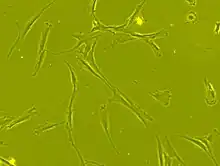

Morphologie

Les CSM ont un corps cellulaire petit, avec quelques éléments cellulaires longs et minces.

Ce corps cellulaire contient un gros noyau rond avec un nucléole proéminent, entouré de fines particules de chromatine dispersées, donnant au noyau une apparence claire.

Le reste du corps cellulaire contient une petite quantité d'appareils de Golgi, un réticulum endoplasmique rugueux, des mitochondries et des polyribosomes.

Ces cellules, longues et minces, sont largement dispersées, et la matrice extracellulaire adjacente est peuplée de quelques fibrilles réticulaires mais dépourvue d’autre types de fibrilles de collagène[39],[36].